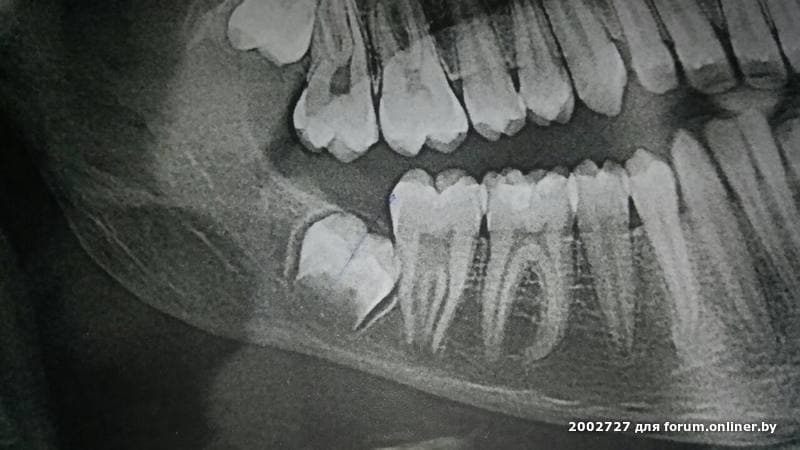

p/p/s/ Мне крайне любопытно, по каким причинам Гричанюк не может удалить 8ки в кресле.